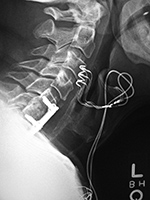

Cranial tongs (lateral view) |

Postoperative lateral radiograph of the cervical spine. There is fixation of an odontoid base fracture by an odontoid screw and a sublaminar wire between C1 and C2. There are also skin staples and a surgical drain in the posterior aspect of the neck |